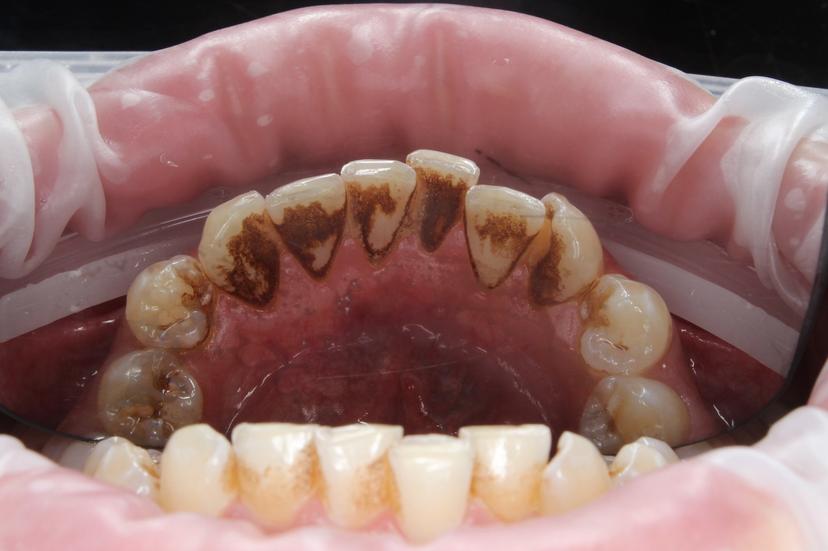

Пигментированный зубной налёт "Присли" у пациента 11 лет.

Профессиональная гигиена проводилась при помощи аппарата Air Flow, позволяющего удалить зубной налёт. Завершающим этапом было полирование зубов, которое позволяет сократить дальнейшее образование налёта.